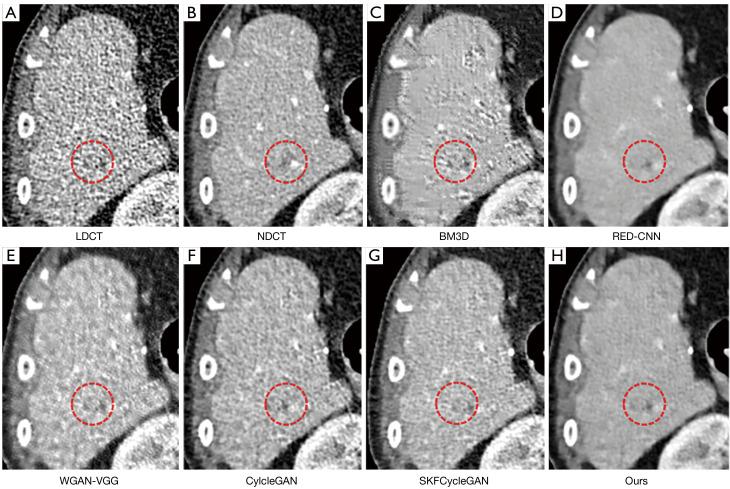

Within the domain of weakly supervised methods, our proposed model exhibited superior objective metrics on the simulated dataset when compared to CycleGAN and selective kernel-based cycle-consistent GAN (SKFCycleGAN): the peak signal-to-noise ratio (PSNR) was 43.9441, the structural similarity index measure (SSIM) was 0.9660, and the visual information fidelity (VIF) was 0.7707. In the clinical dataset, we conducted a visual effect analysis by observing various tissues through different observation windows. Our proposed method achieved a no-reference structural sharpness (NRSS) value of 0.6171, which was closest to that of the NDCT images (NRSS =0.6049), demonstrating its superiority over other denoising techniques in preserving details, maintaining structural integrity, and enhancing edge contrast.

CONCLUSIONS

Through extensive experiments on both simulated and clinical datasets, we demonstrated the superior efficacy of our proposed method in terms of denoising quality and quantity. Our method exhibits superiority over both supervised techniques, including block-matching and 3D filtering (BM3D), residual encoder-decoder convolutional neural network (RED-CNN), and Wasserstein generative adversarial network-VGG (WGAN-VGG), and over weakly supervised approaches, including CycleGAN and SKFCycleGAN.

结果

在弱监督方法领域,与CycleGAN和基于选择性内核的循环一致GAN(SKFCycleGAN)相比,我们提出的模型在模拟数据集上表现出更好的客观指标:峰值信噪比(PSNR)为43.9441,结构相似性指数测量(SSIM)为0.9660,视觉信息保真度(VIF)为0.7707。在临床数据集中,我们通过不同观察窗口观察各种组织进行了视觉效果分析。我们提出的方法实现了无参考结构清晰度(NRSS)值为0.6171,最接近NDCT图像的NRSS值(NRSS = 0.6049),表明其在保留细节、保持结构完整性和增强边缘对比度方面优于其他去噪技术。

结论

通过在模拟和临床数据集上进行的大量实验,我们证明了我们提出的方法在去噪质量和数量方面具有卓越的效果。我们的方法在包括块匹配和3D滤波(BM3D)、残差编码器 - 解码器卷积神经网络(RED - CNN)以及瓦瑟斯坦生成对抗网络 - VGG(WGAN - VGG)等监督技术,以及包括CycleGAN和SKFCycleGAN等弱监督方法方面均表现出优越性。